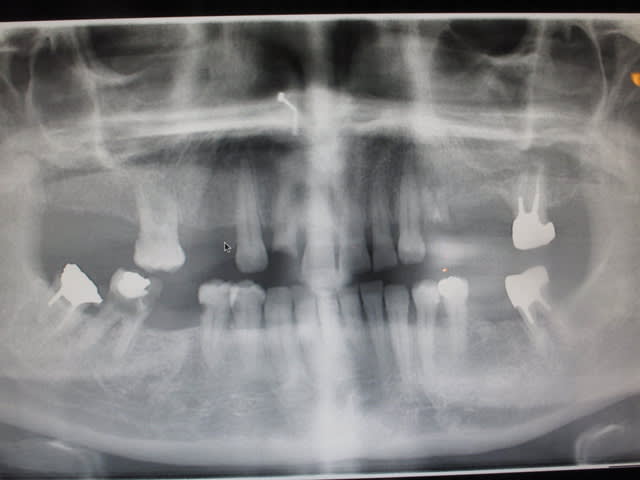

Une pano serait t'elle disponible?

Pano? Selon l'état des dents résiduelles, l'idée générale ne sera pas la même...

Je vous joint la pano.

Img 3760 wivma4 - Eugenol

Pour la pano il manque les condyles !

Si les condyles sont bien positionné avec le plan occlusal "de travers" comme sur cette pano, le plan de traitement change complètement.

Avant même d'essayer de déterminer votre DV il faut savoir si le plan d'occlusion est incliné de cette manière car les dents ne sont pas au même niveau du coté droit et gauche, si le problème se situe dans l'os alvéolaire ou si il s'agit d'une asymmetrie des bases squelettique.

Une fois que l'origine de cette asymmetrie verticale connue on peut commencer a envisager les différentes solution pour régler le problème.